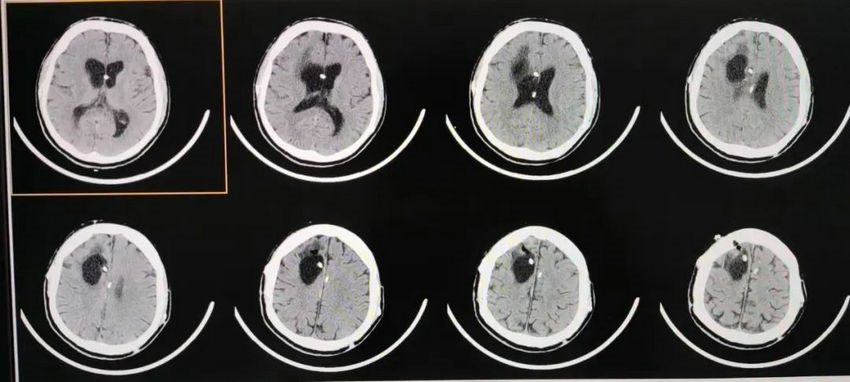

▲ 术后半个月头颅CT显示:侧脑室旁囊肿与侧脑室沟通,侧脑室旁囊肿大小及脑室大小变化不大